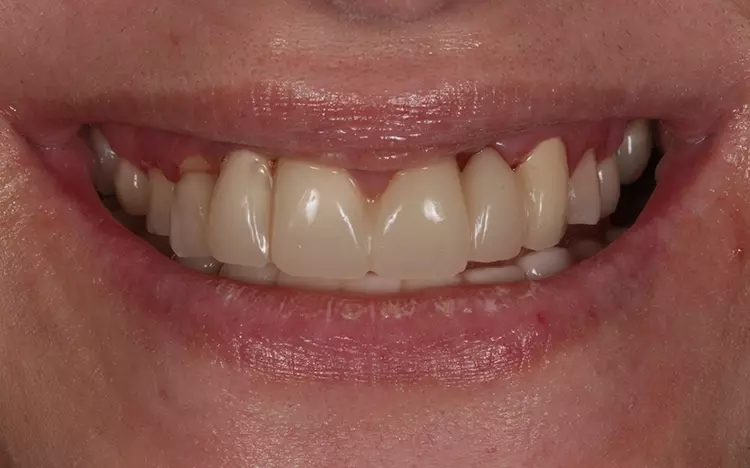

Aufgrund der klinischen Beschwerdefreiheit und auch der Tatsache, dass Heilungs- und Umbauvorgänge im Gelenk noch stattfinden können, soll vorerst noch 6 bis12 Monate bei regelmäßiger klinischer Nachkontrolle abgewartet werden. Die Patientin ist subjektiv beschwerdefrei (keine Anzeichen einer Dekompensation in der klinischen Funktionsanalyse). Zudem äußert sie keine Druckdolenz der Kaumuskulatur und/oder der Gelenke [22,23] (Abb. 19 bis 22).